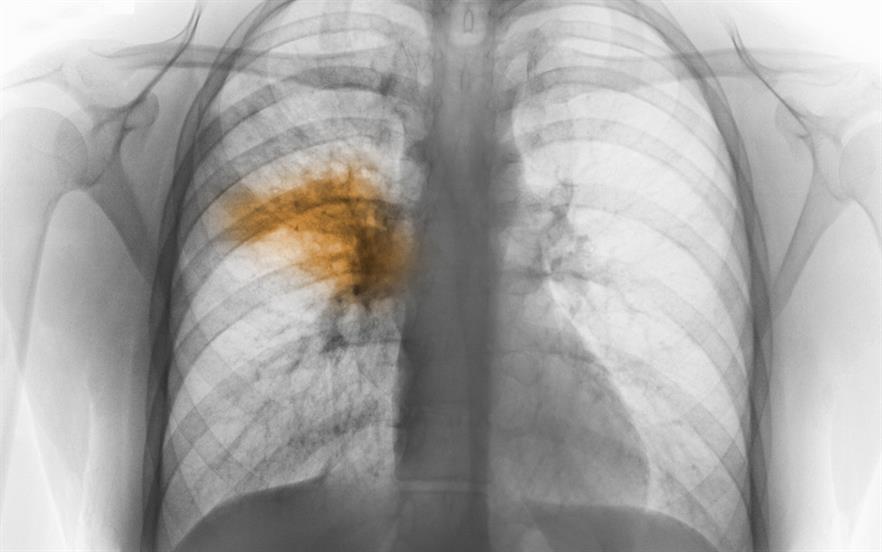

How Long Does It Take Antibiotics To Work On Pneumonia . A course of antibiotics for uncomplicated pneumonia treatment usually lasts five to seven days. If you have bacterial pneumonia, you’re no longer considered contagious when your fever is gone and you’ve been on antibiotics for at least two days. Specific treatments depend on the type and severity of your pneumonia, your age and your overall health. The appropriate antibiotics for bacterial pneumonia depend on your specific infection, overall health, and local patterns of. If your pneumonia is caused by bacteria, you will be given an antibiotic. How to take antibiotics for pneumonia. If a person has severe complications, such as a lung abscess , it may take four to. Most people who are treated for bacterial pneumonia start feeling better in a few days, but it can take a few weeks before you. When treated with antibiotics, many cases of pneumonia last about two to three weeks. It is important to take all the antibiotic until it is gone, even though you will probably start to feel better in.